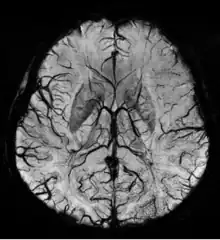

Stroke and hemorrhage

Diffusion weighted imaging offers a powerful means to detect acute stroke. Although it is well known that gradient echo imaging can detect hemorrhage, it is best detected with SWI. In the example shown here, the gradient echo image shows the region of likely cytotoxic edema whereas the SW image shows the likely localization of the stroke and the vascular territory affected (data acquired at 1.5 T).

The bright region in the gradient echo weighted image shows the area affected in this acute stroke example. The arrows in the SWI image may show the tissue at risk that has been affected by the stroke (A, B, C) and the location of the stroke itself (D). The reason that we are able to see the affected vascular territory could be because there is a reduced level of oxygen saturation in this tissue, suggesting that the flow to this region of the brain could be reduced post stroke. Another possible explanation is that there is an increase in local venous blood volume. In either case, this image suggests that the tissue associated with this vascular territory could be tissue at risk. Future stroke research will involve comparisons of perfusion weighted imaging and SWI to learn more about local flow and oxygen saturation.